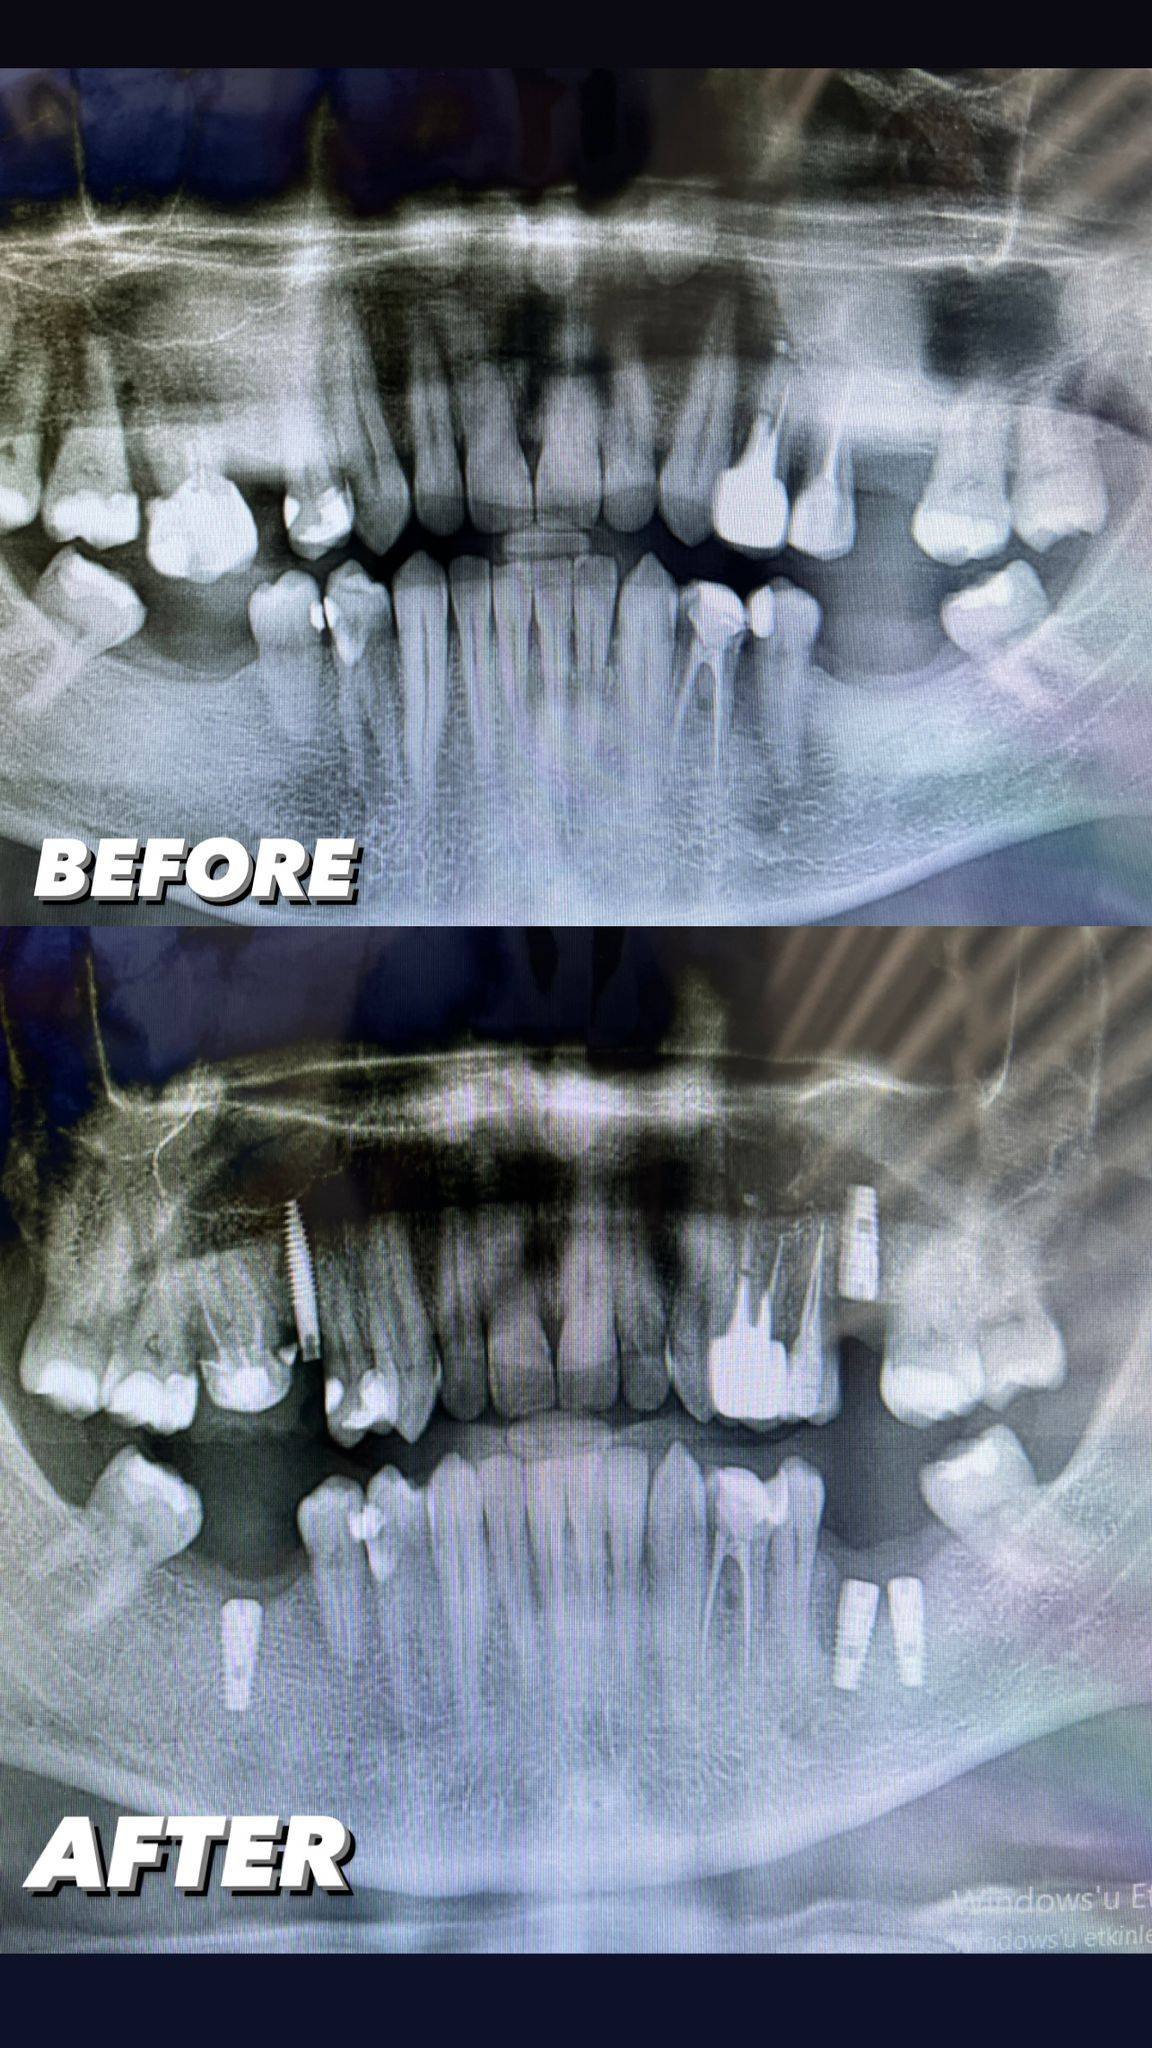

Ağızda eksik olan diş veya dişleri tamamlamak için çeneye yerleştirilen vida ya da vidalar yardımıyla yapılan tedavidir. Eksik olan dişler bu vidaların üzerine yerleştirilmektedir. Tek bir diş için uygulanabileceği gibi uzun diş boşluklarında da bu tedavi yöntemi kullanılabilmektedir. Kişinin kemik yapısının sağlamlığı ve diş eti sağlığı tedavide başarıyı artırmaktadır.

implant tedavisi uygulandıktan sonra normal bekleme 3 ay olan ve bu süre zarfı sonunda üzerine eklenen zirkonyum kaplamayı. Bekleme sürecini 3 aydan , 72 saat’e başarılı bir şekilde düşürüyoruz.